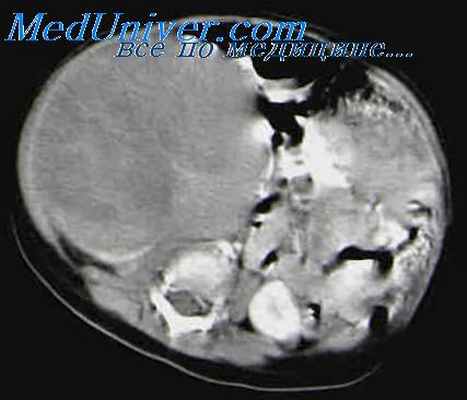

Термографию активно используют для диагностики патологии сосудов (рис. 1). При нарушении артериального кровообращения (ангиоспазм, сужение или полный стеноз сосуда) определяется зона гипотермии, которая по положению, форме и размерам соответствует области снижения кровотока. При патологии венозных сосудов, напротив, обычно выявляют зону гипертермии [9].

Рис. 1. Термографическая диагностика заболеваний сосудов: а — облитерирующий атеросклероз сосудов нижних конечностей; б — варикозное расширение вен нижних конечностей

Локальное повышение температуры в области поверхностных вен нижних конечностей указывает на вероятность тромбофлебита. Атеросклеротические изменения сосудов также ведут к нарушению кровотока и изменению температуры, что позволяет зафиксировать наличие атеросклеротических бляшек методом термографии [16, 20]. Возможно применение методики в эндоваскулярной хирургии [21].